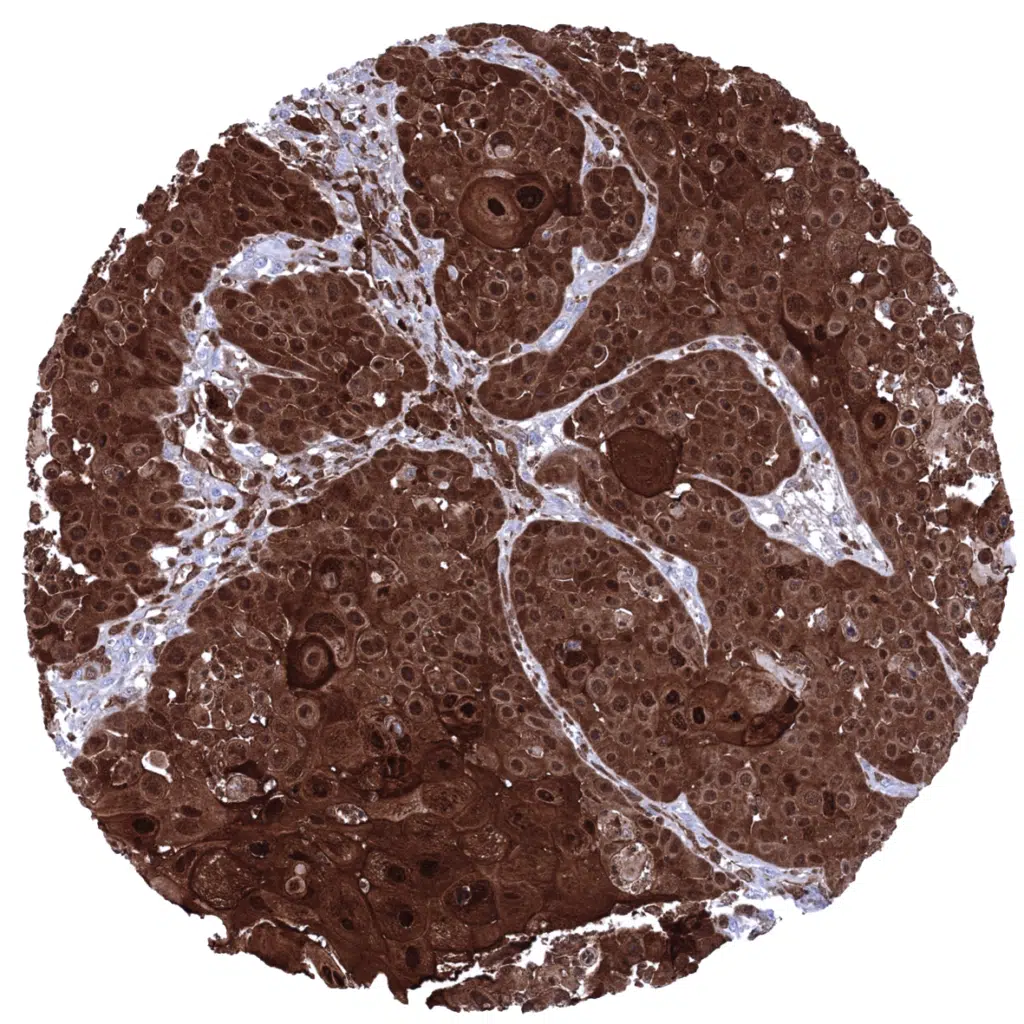

Salivary gland- Warthin tumor with variable intensity Cystatin A immunostaining of tumor cells. Cystatin A is also strongly expressed in tumor associated dendritic cells.